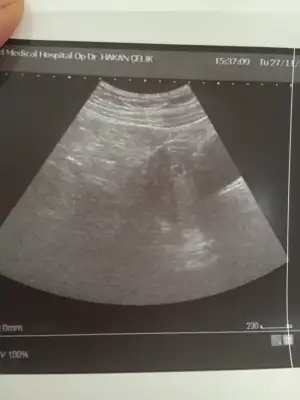

Merhaba kizlar bu gün kesem gözüktü 4+6 dedi doktor burdan biri kese hangi taraftaysa ona göre cinsiyet tahmin ediyordu kimdi o

Eklentiler

• 21C70EF8-FDCE-419D-855C-3E9D7842D1C5.webp

21C70EF8-FDCE-419D-855C-3E9D7842D1C5.webp

27,1 KB · Görüntüleme: 45